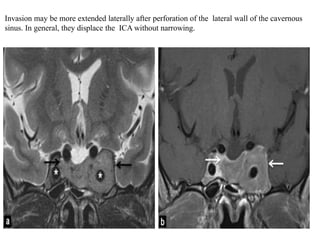

Invasion may be more extended laterally after perforation of the lateral wall of the cavernous

sinus. In general, they displace the ICA without narrowing.

Invasion may bemore extended laterally after perforation of the lateral wall of the cavernous sinus. In general, they displace the ICA without narrowing.

• #27 Pituitary adenoma. Coronal T2-wi (a) and coronal enhanced T1-wi (b) showing an enhancing pituitary adenoma (arrows), appearing hyperintense on T2-wi and invading the left cavernous sinus with an encasement of the left internal carotid artery. Note the displacement of the arteries by the mass (stars) without stenosis.